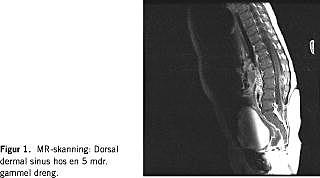

En akut MR-skanning af cerebrum og columna viste en væskefyldt sinus fra hudoverfladen i højde med L-4, som gik ind i spinalkanalen i højde med L-5, hvor den endte i en proces, der lignede en epidural absces, beliggende bag corpus L 3/4. MR-skanningen gav ikke mistanke om tethered cord (Figur 1 ). Ved akut operation viste der sig at være tale om et intraspinalt lipom. Lipom og sinus blev fridissekeret og fjernet. Patienten fik herefter tre ugers antibiotikaterapi først i form af ampicillin/ceftriaxon givet intravenøst og fra tredje døgn postoperativt i form af cefuroxim givet intravenøst.